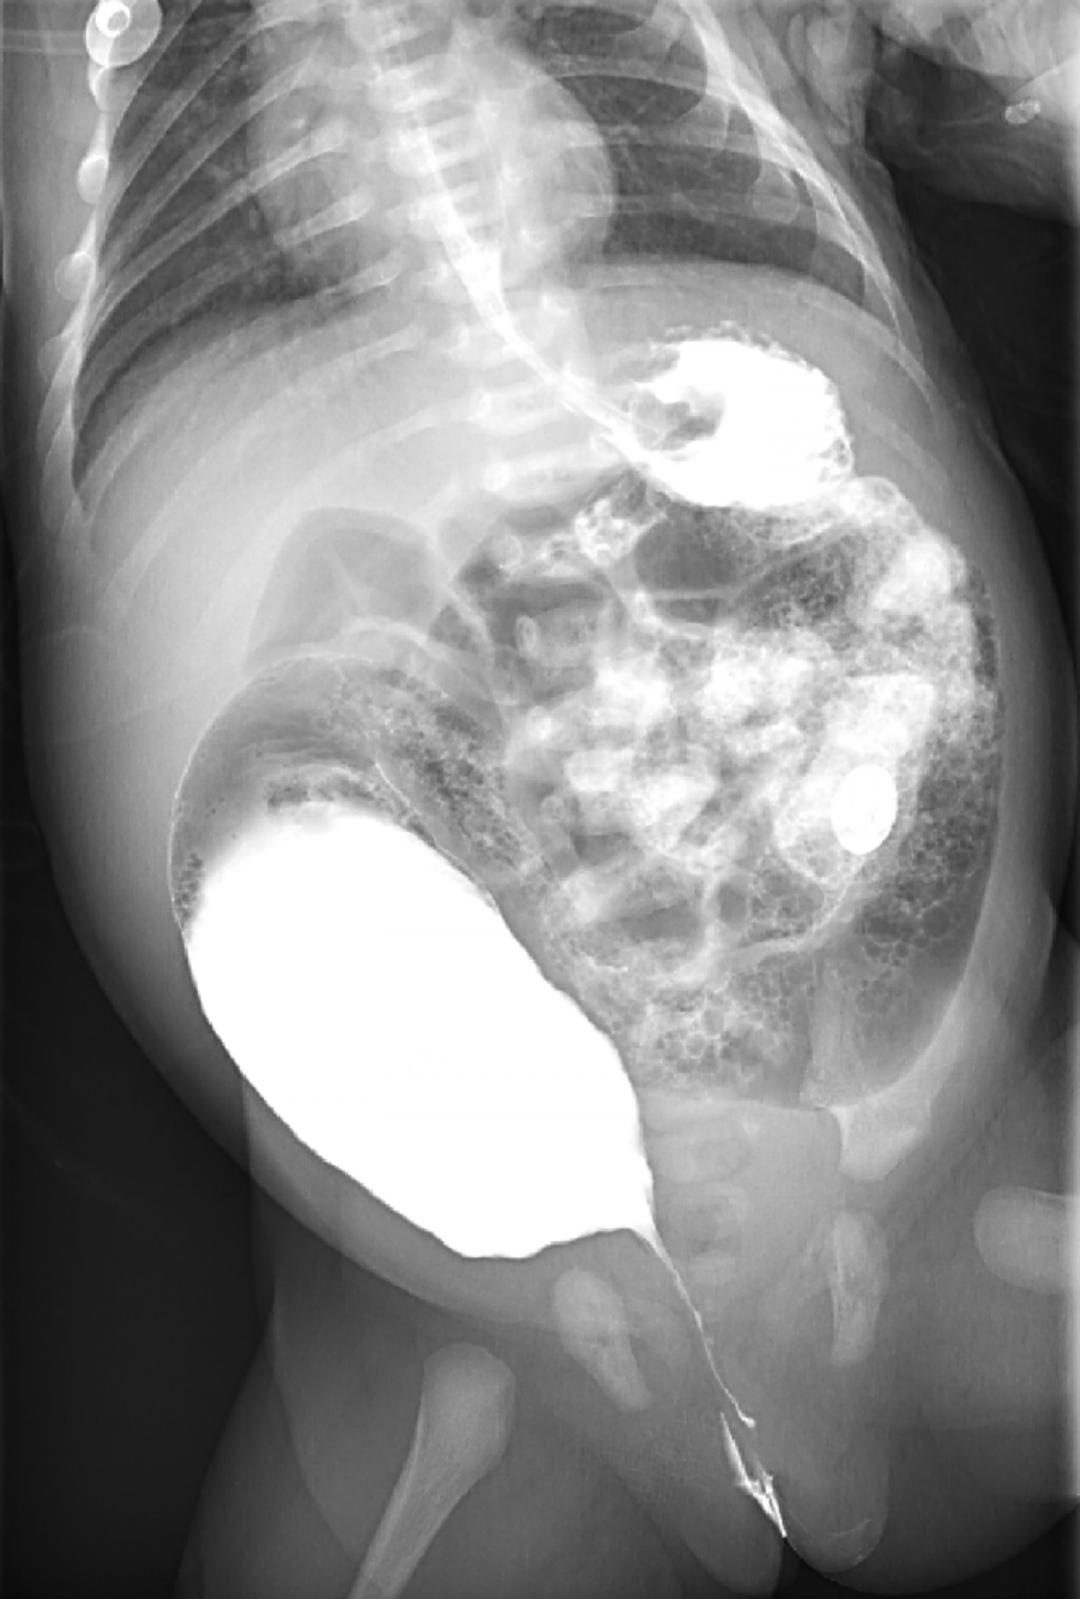

⬆️

(消化道造影结果图)

在告知患儿家属病情及诊疗方案,并征得家属理解和支持后,由儿外科主任周小渔教授为小宝进行了 “经会阴肛门成形术” ,通过扩张瘘口实现小宝排便功能,术后,小宝恢复良好,三个月后待行二期手术。